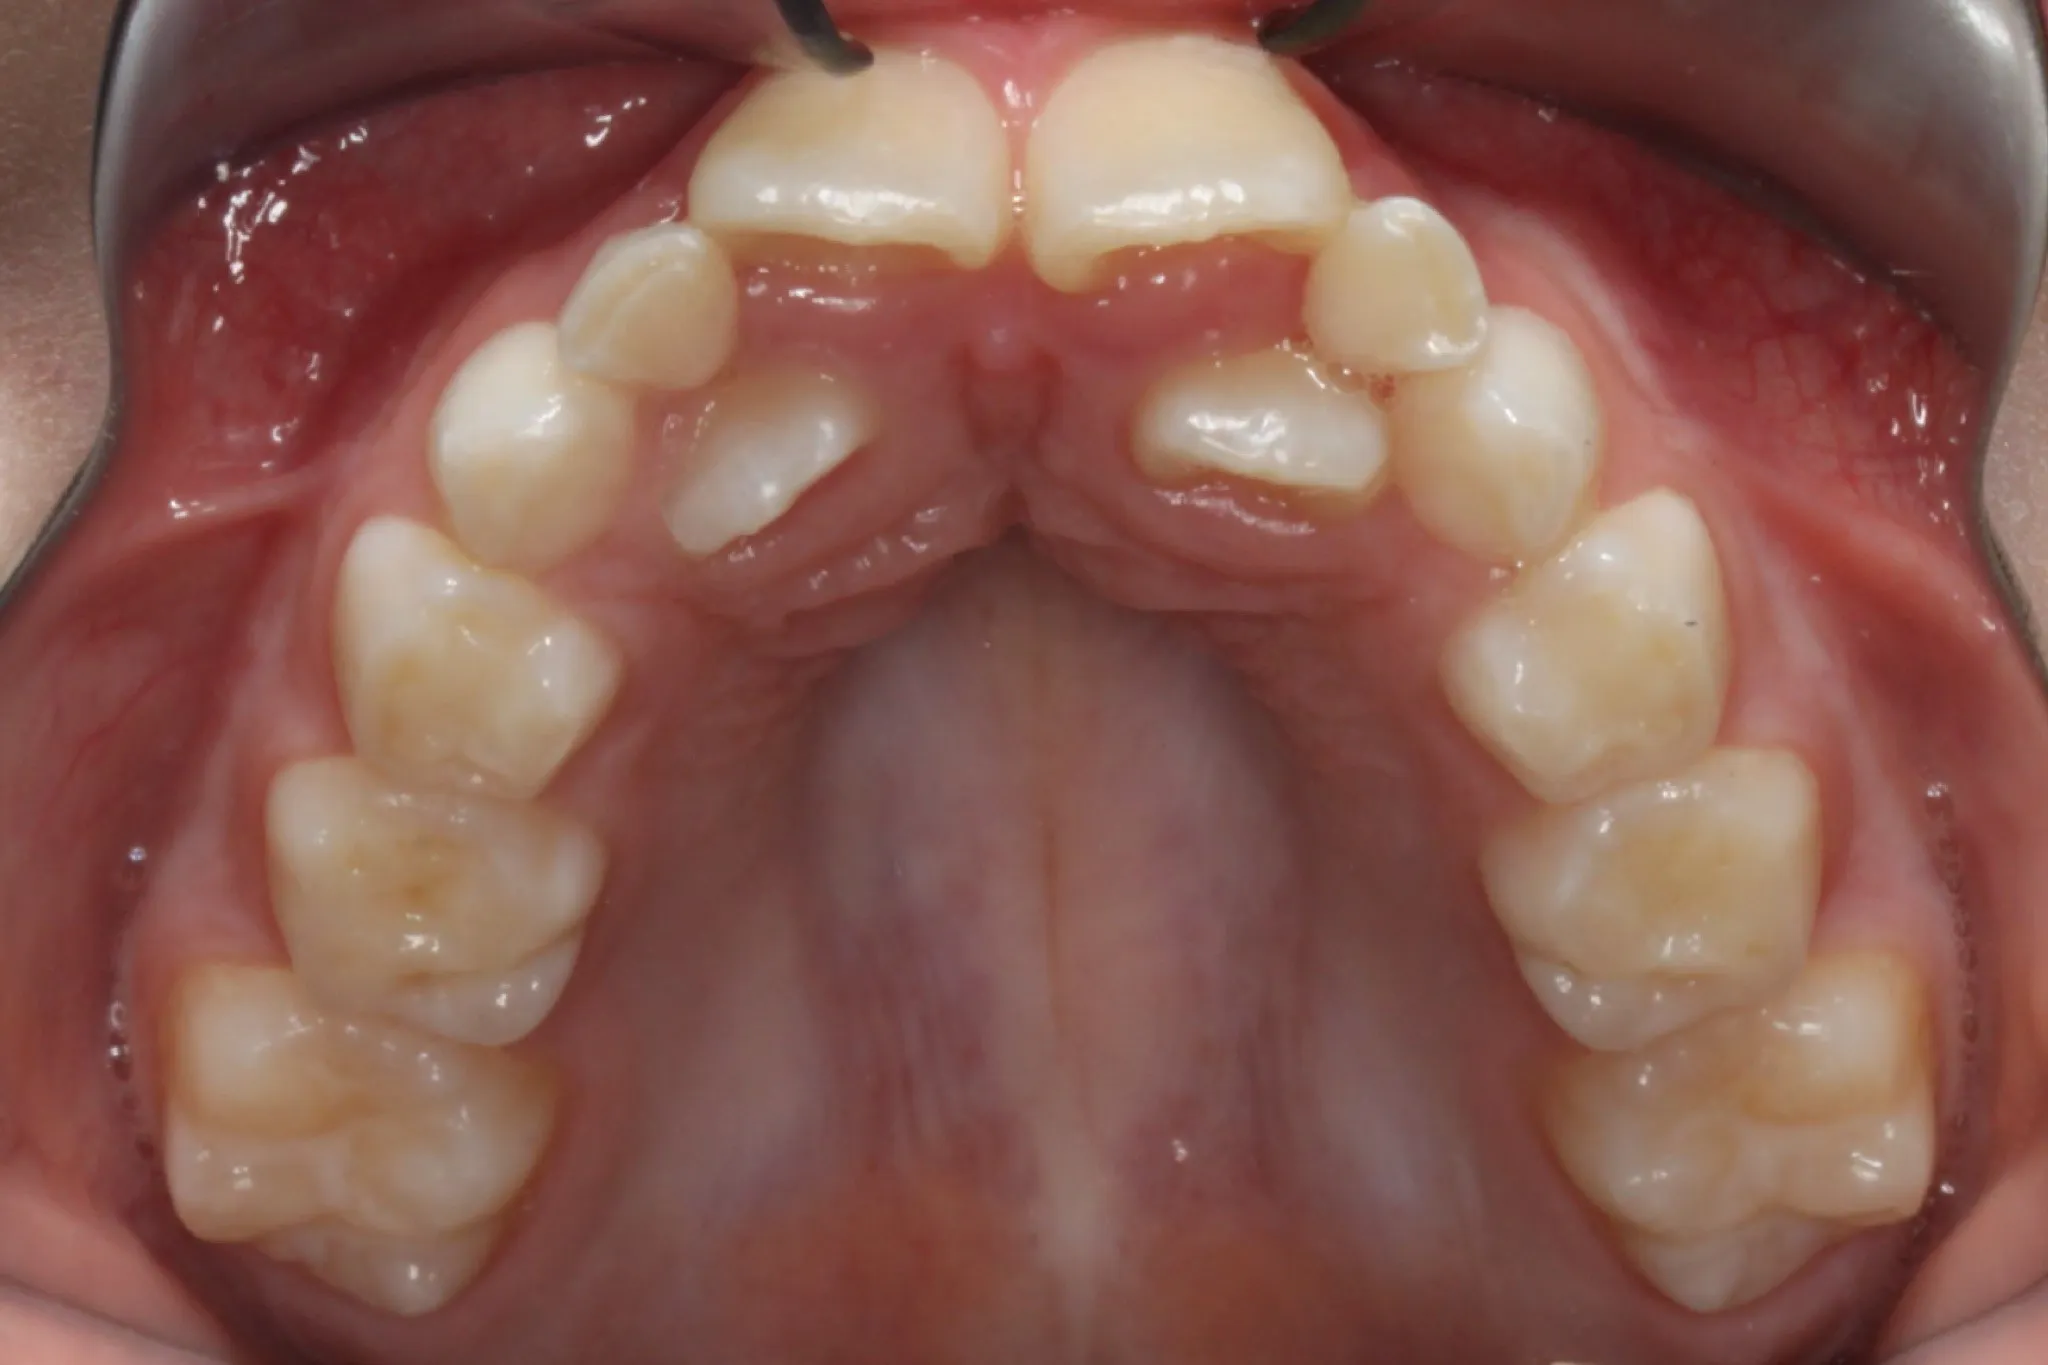

Patient T.G. Dental crowding, crossbite > Expander, extractions Expander Braces Time One common characteristic of a palate expander is a noticeable gap between the front teeth. Rapid palate expanders can widen your jaw at a rate of 0.5 millimeters per day. It is used to widen a narrow maxilla (upper jaw). This gap will be closed using braces with time and will not be there permanently. A palate expander — also. Expander Braces Time.